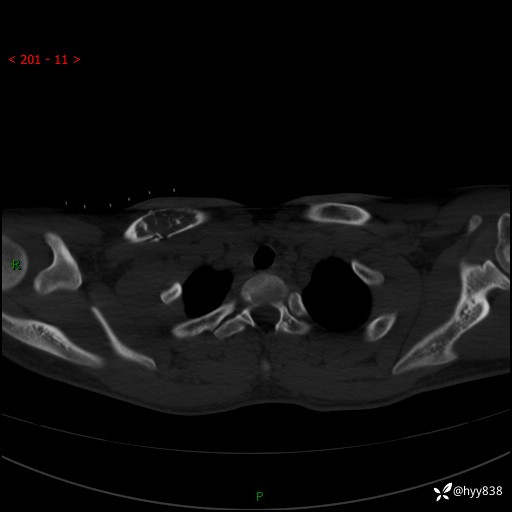

CT